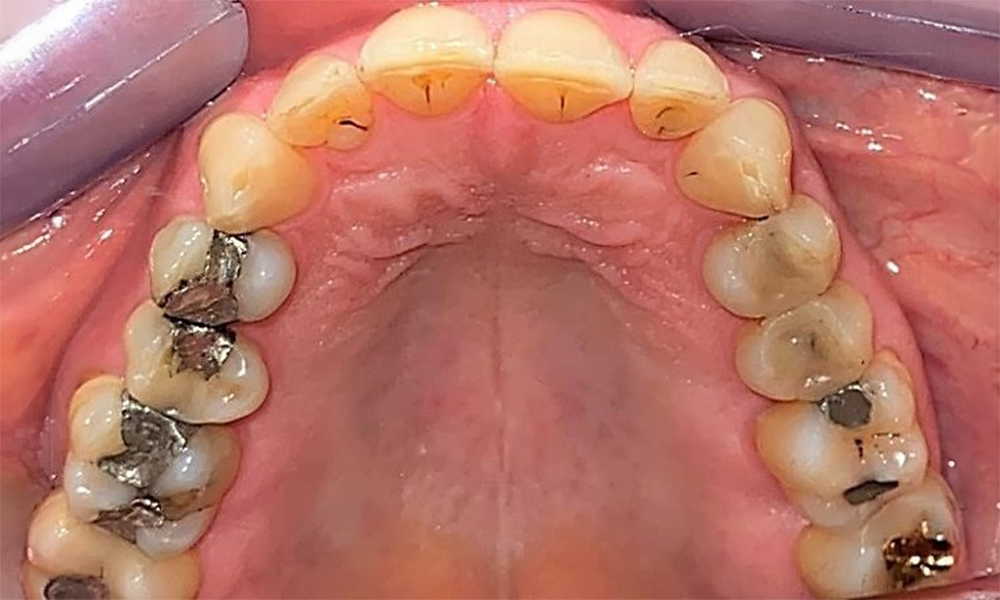

Pacientul prezintă dentiție completă cu 28 de dinți, care include obturații din amalgam și compozit pe molari și premolari. Există un spațiu marginal clinic vizibil la 14. Molarul 27 prezintă un inlay din aur adecvat. Se observă, de asemenea, atriții și abrazii generalizate. (Fig. 2, Fig. 3, Fig. 4, Fig. 5, Fig. 6)

Pacientul prezintă boală parodontală în stadiul II, gradul B (5). Profunzimile clinice de sondare observate, între 1 și 3 mm, se încadrează în limitele fiziologice. Localizat, s-au observat profunzimi de 5 mm, la nivel meziopalatin, atât pe 17, cât și pe 27. Se constată recesiuni generalizate de 1-3 mm, cu pierderi parțiale ale papilelor interdentare (Fig. 2, Fig. 3, Fig. 4)